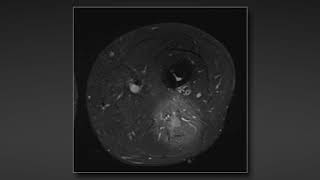

Surgical repair of sciatic nerve traumatic rupture: technical considerations and approaches

Hussam Abou-Al-Shaar, MD, Nam Yoon, MD, and Mark A. Mahan, MD Department of Neurosurgery, Clinical Neurosciences Center, University of Utah, Salt ...

AANSNeurosurgery